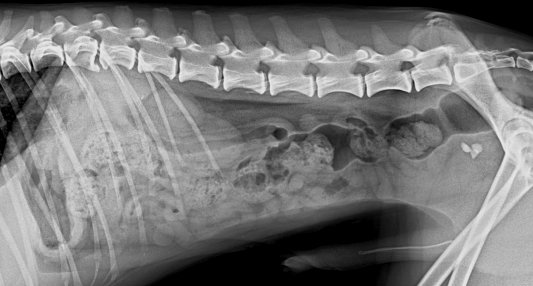

- 진단: 신체검사, 소변검사, 영상검사(방사선, 초음파 등)로 결석을 진단할 수 있습니다.